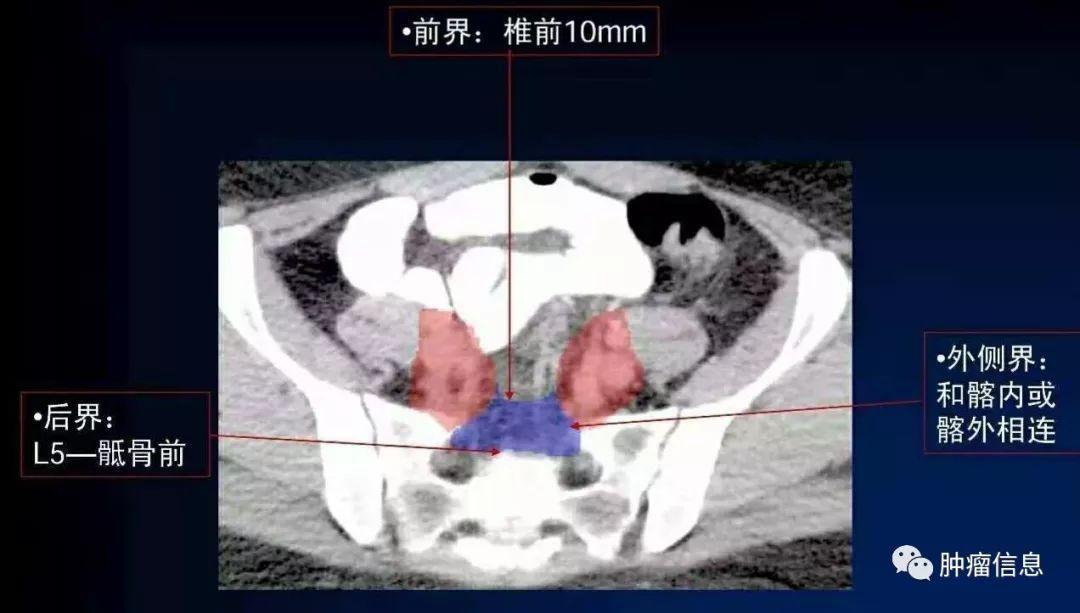

骶前淋巴结

图中蓝色区域上界:髂总分叉下界:S2下缘或梨状肌上缘其他边界见下图: